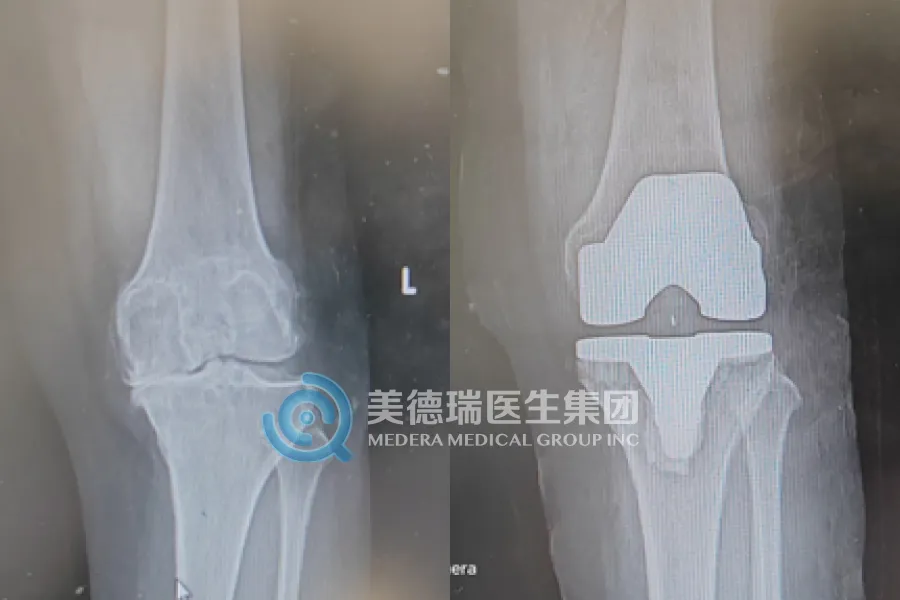

近期,该中心已常态化开展包括膝关节置换、人工股骨头置换、关节镜下半月板缝合、腰椎融合及椎板减压术等在内的多项核心术式,覆盖了关节、脊柱、运动医学等多个领域,标志着中心已从单纯的“技术引入”迈向了“能力扎根”的全新阶段,区域骨科诊疗水平实现了实质性的飞跃。

- 对于备受膝关节炎折磨的老人,人工膝关节置换术能有效缓解疼痛,显著改善关节功能,让他们重新享受行走的自由。